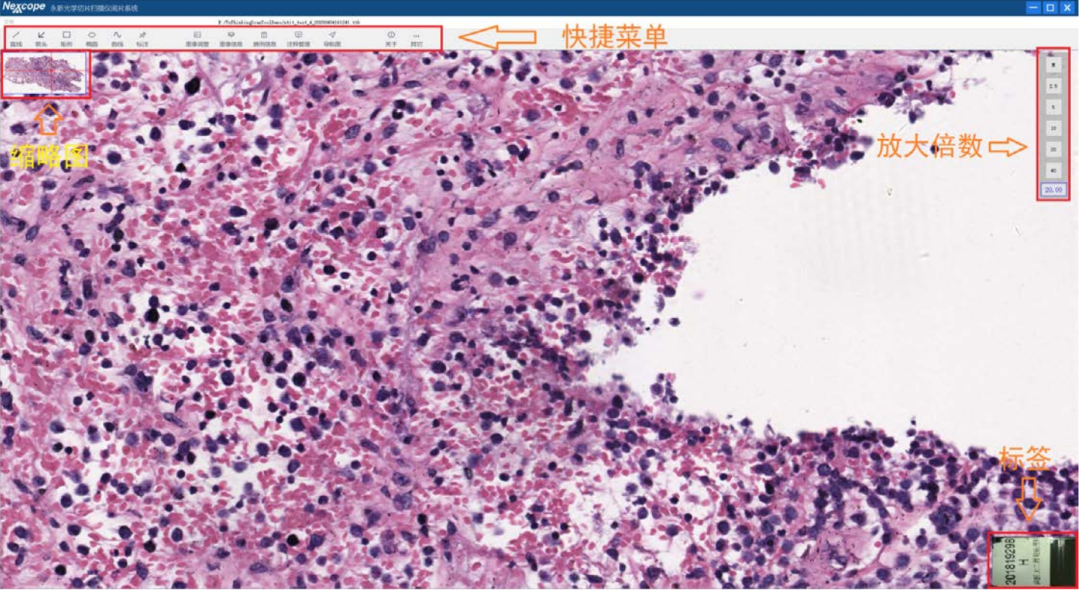

18.5、支持浏览不同扫描倍数下的全景信息数字化玻片,可进行注释、标记,同时可对标注进行导航定位,快速找到标注区域。浏览放大倍率支持固定倍率放大及无级放大,最大可支持100X放大倍率;

专业的图像扫描、管理与浏览软件

图片管理与浏览

图像存储与导入功能以对实验数据进行长期存档;图像压缩格式支持 : 支持 JPEG、TIFF、BMP 等格式;浏览不同扫描倍数下的全景信息数字化玻片,可进行注释、标记;可形成标准教学示范图集,用于教学;